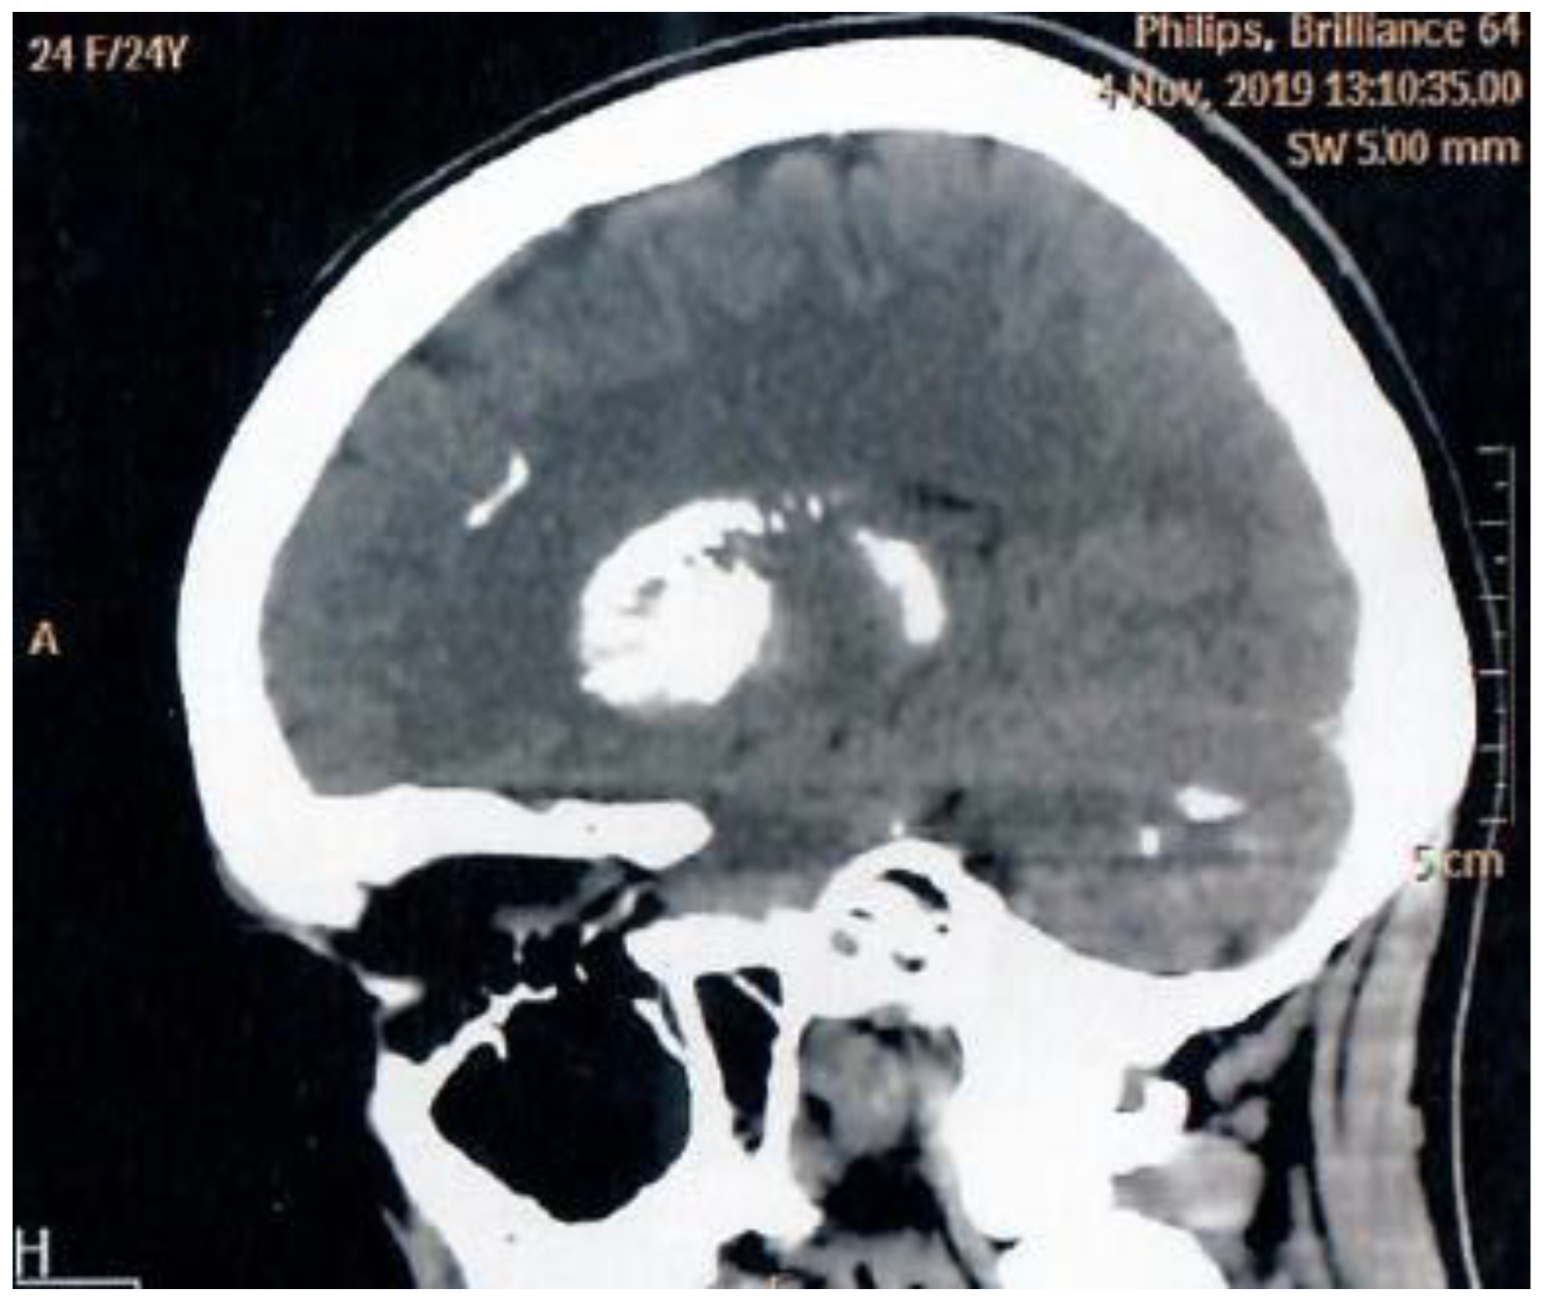

Neurological status remained stable with no progression of Fahr syndrome on brain imaging (Figure 1). Annual monitoring showed preserved kidney function (eGFR 112.3 mL/min/1.73 m²), with no ultrasound-signs of nephrocalcinosis, nephrolithiasis, and cardiac calcification. Ophthalmologic evaluation revealed only mild myopia without lens pathology. Additional findings included erosive gastritis (positive parietal cell antibodies) and normal bone mineral density (BMD). The patient continues regular check-ups in our Centre.

Figure 1. MRI scan of patient`s brain (Fahr syndrome).